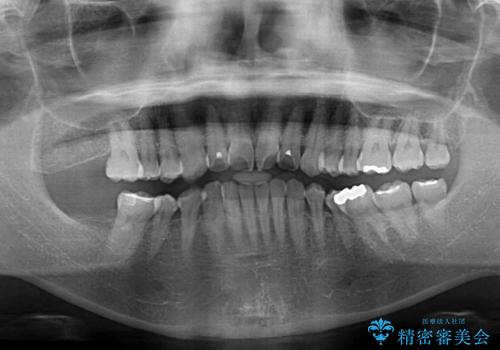

- 上下前歯の叢生を気にして来院された患者様です。

費用を抑え、期間もあまりかけずに治療をしたいとのことで、インビザライン・ライトを用いて矯正治療を行うこととしました。

インビザライン・ライトは、製作できるアライナーの枚数に制限があるため、移動可能な量に限りがあります。

一方で、半年から1年程度で治療を終えることができるため、軽度の歯列不正の患者様には大変お勧めです。